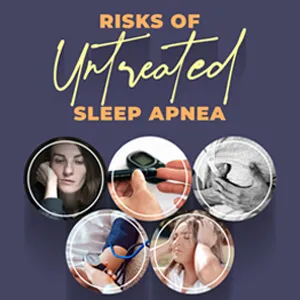

Read more5 Risks of Untreated Sleep Apnea

Do you wake up in the middle of the night, in between sleep, with breathing troubles? Do you always seem to be in a state of fatigue throughout the day while working? Do you wake up with repetitive morning headaches?

Sleep apnea is a severe sleeping condition that can deteriorate into severe health disorders if left untreated for a long time. Also, individuals dealing with sleep apnea experience interrupted breathing, while sleeping, for more than a hundred times.